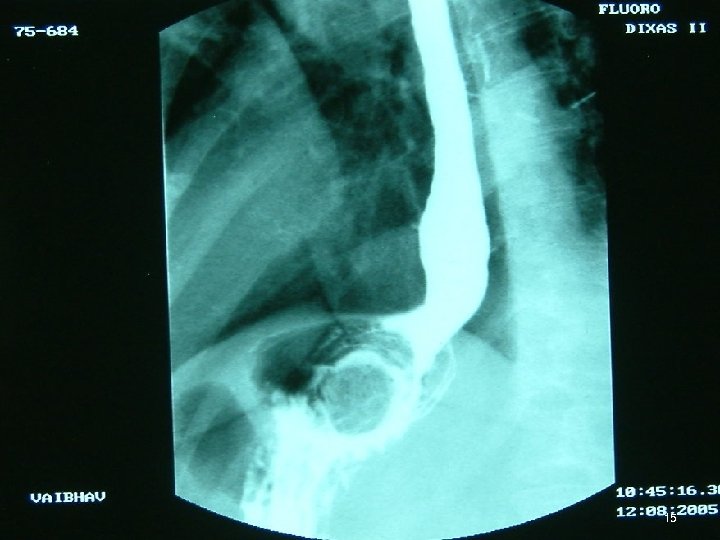

Investigations • • • Chest X Ray USG CECT EUS Ba Swallow 3

4

5

6

7

8

Diagnosis • GIST, Lymphoma / 2 nd primary at GI jn ♠ Submucosal ≡ ► ►GIST = first diagnosis